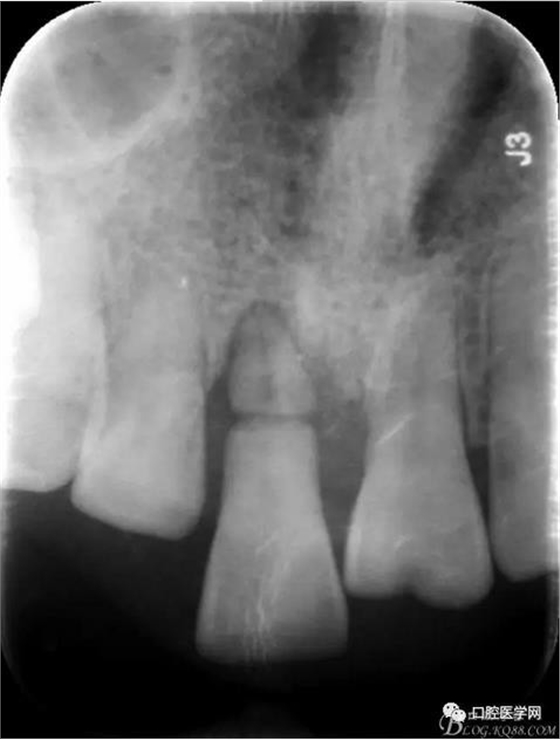

檢 查:11 伸長約2-3mm,松動III°,牙齦退縮3mm

X 光 示:11 根折,根尖無明顯異常

診 斷:11 根折

圖1 術前X光片